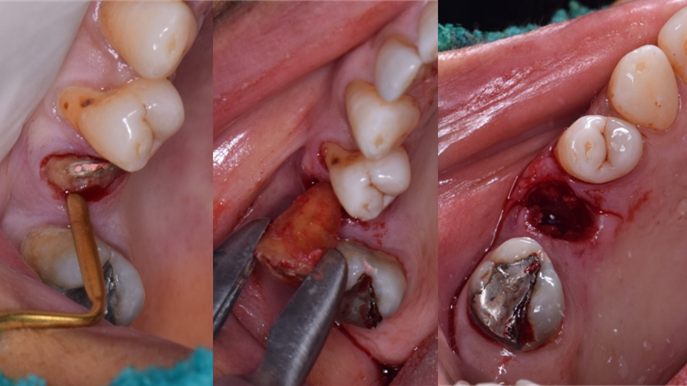

“Does guided surgery always mean flapless surgery? ”

Clinical case: R2GATE GUIDE surgery with GBR

- Courtesy of Dr. Kwang Bum Park, Korea -

Dr. Kwang Bum Park, digital guided surgery, bone regeneration, maxillary posterior, #13, #14, guided surgery, GBR, AnyRidge, i-GEN, Mega-Oss, R2GATE, R2GATE Full surgical kit